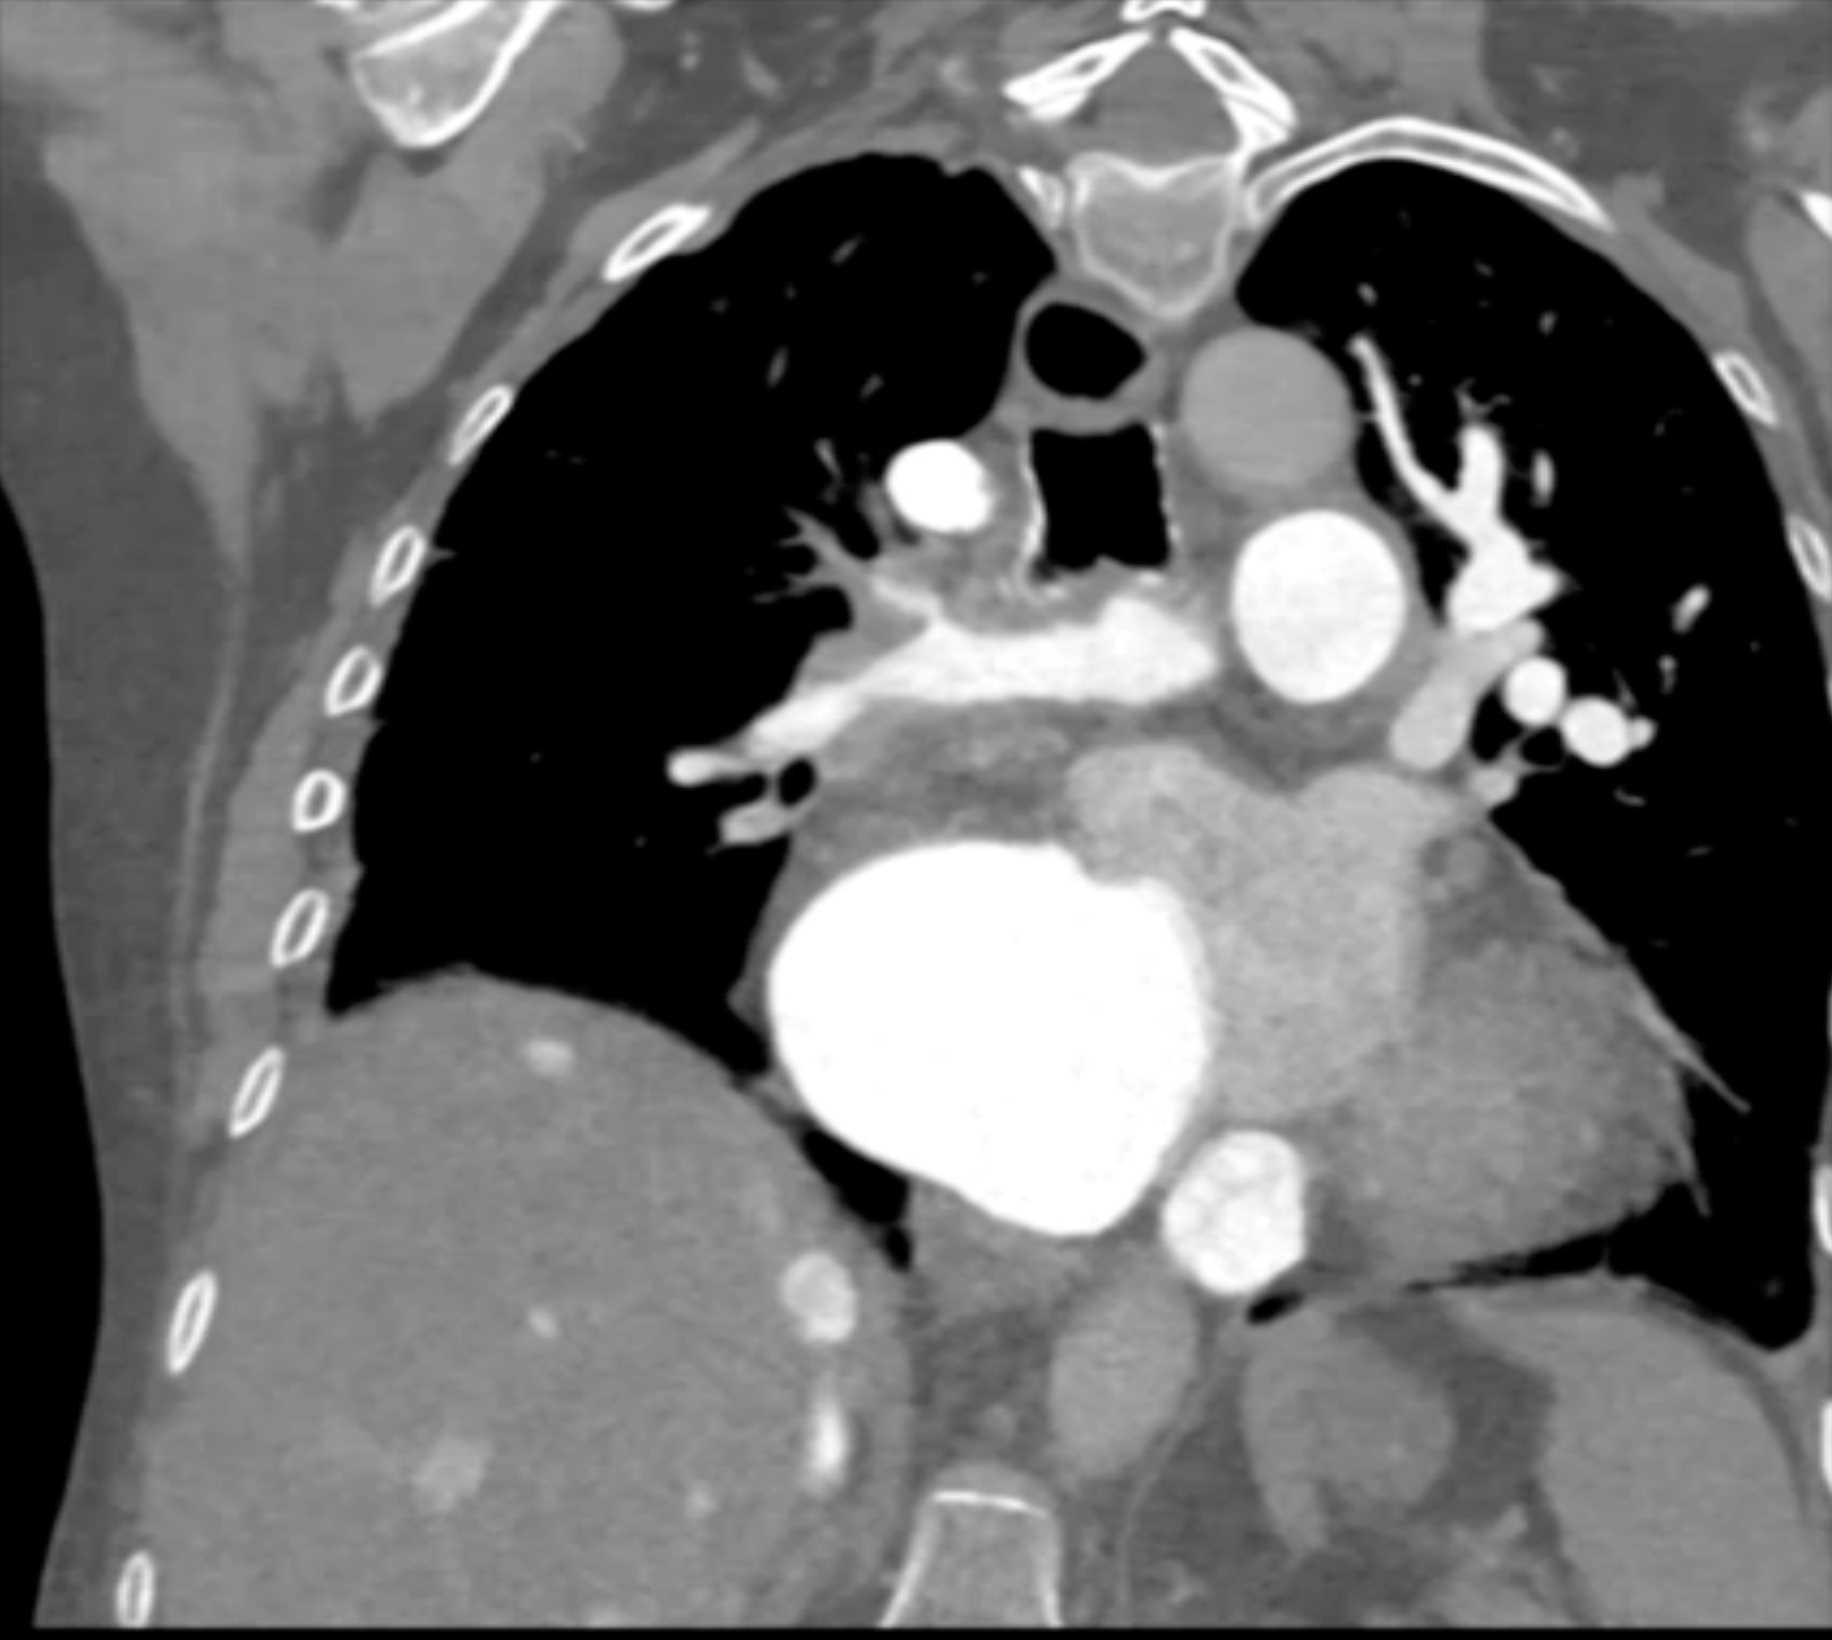

Fibrosing Mediastinitis involves the Pulmonary Artery and Vein